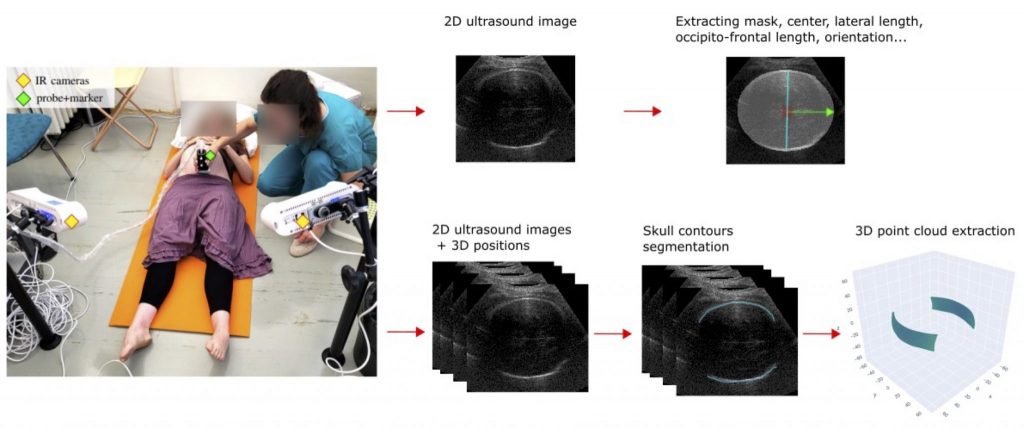

2. Deep learning for foetal head segmentation on 3D-tracked ultrasound images

Due to its non-invasive nature, ultrasound imaging is a widely employed technique in the field of obstetrics and gynaecology. It relies on emitting ultrasound waves into tissues and receiving echoes produced at tissue interfaces.

By integrating ultrasonography with an optical tracking system, such as infrared cameras and a reflective marker on the ultrasound probe, 3D-tracked ultrasound imaging enables the continuous recording of the image plane’s position in 3D space. By employing this technique, we can reconstruct large volumes and achieve 4D visualization by fitting 3D models to the generated images and point clouds. In the frame of a larger project in obstetrics*, we aim to develop such visualization system for the foetal head during childbirth.

One crucial step towards this goal is the automatic and real-time segmentation of the foetal head on ultrasound images. The segmentation process would consist of two main parts. First, we need to extract a mask and biometric parameters from independent 2D images. Second, we need to accurately segment the fine contours of the skull from a set of 3D-tracked images to extract a 3D point cloud.

We are looking for a Master student to work on those two segmentation steps. The first part will involve the development and application of a deep learning approach, incorporating techniques such as transfer learning, data augmentation and the design of a task-specific training loss. For the second part, the student will develop a method utilizing the 3D spatial consistency amongst ultrasound images.

2. Deep learning for foetal head segmentation on 3D-tracked ultrasound images

Due to its non-invasive nature, ultrasound imaging is a widely employed technique in the field of obstetrics and gynaecology. It relies on emitting ultrasound waves into tissues and receiving echoes produced at tissue interfaces.

By integrating ultrasonography with an optical tracking system, such as infrared cameras and a reflective marker on the ultrasound probe, 3D-tracked ultrasound imaging enables the continuous recording of the image plane’s position in 3D space. By employing this technique, we can reconstruct large volumes and achieve 4D visualization by fitting 3D models to the generated images and point clouds. In the frame of a larger project in obstetrics*, we aim to develop such visualization system for the foetal head during childbirth.

One crucial step towards this goal is the automatic and real-time segmentation of the foetal head on ultrasound images. The segmentation process would consist of two main parts. First, we need to extract a mask and biometric parameters from independent 2D images. Second, we need to accurately segment the fine contours of the skull from a set of 3D-tracked images to extract a 3D point cloud.

We are looking for a Master student to work on those two segmentation steps. The first part will involve the development and application of a deep learning approach, incorporating techniques such as transfer learning, data augmentation and the design of a task-specific training loss. For the second part, the student will develop a method utilizing the 3D spatial consistency amongst ultrasound images.